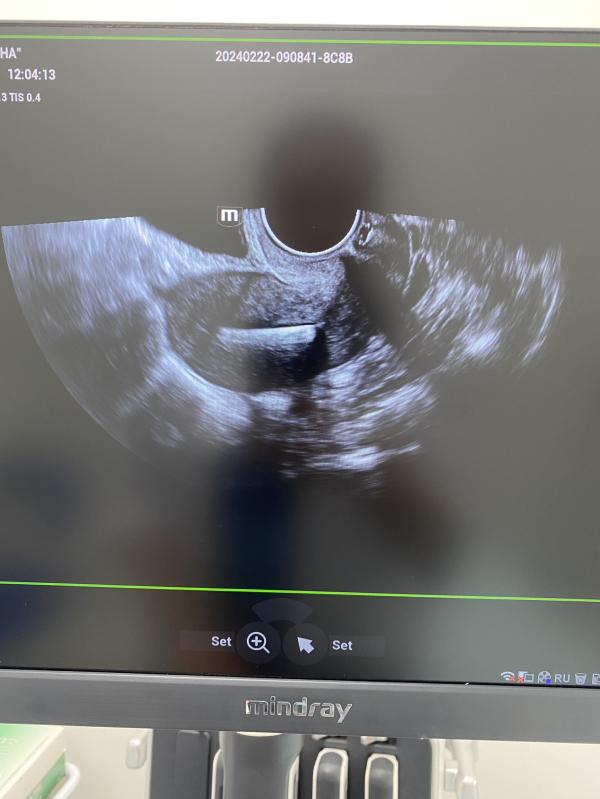

post image 1